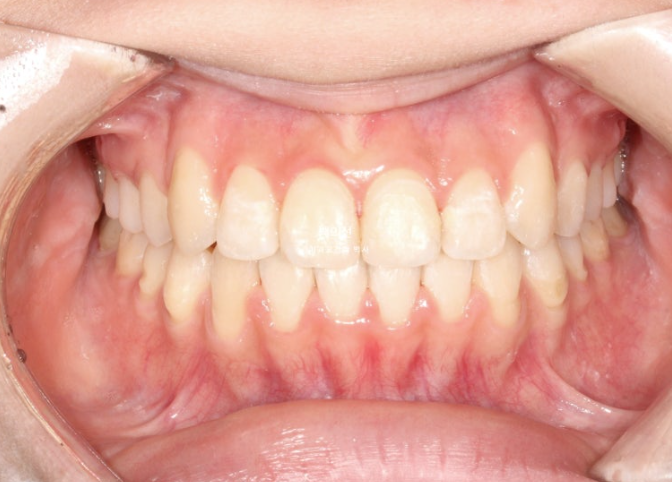

25.07

교합은 좌우 정 1급을 달성했으며 좋습니다.

이제 전후 비교 보겠습니다.

돌아가있던 송곳니 덧니가 해소가 되며 입동굴이 시원하게 생겼습니다.

깔끔해진 미소